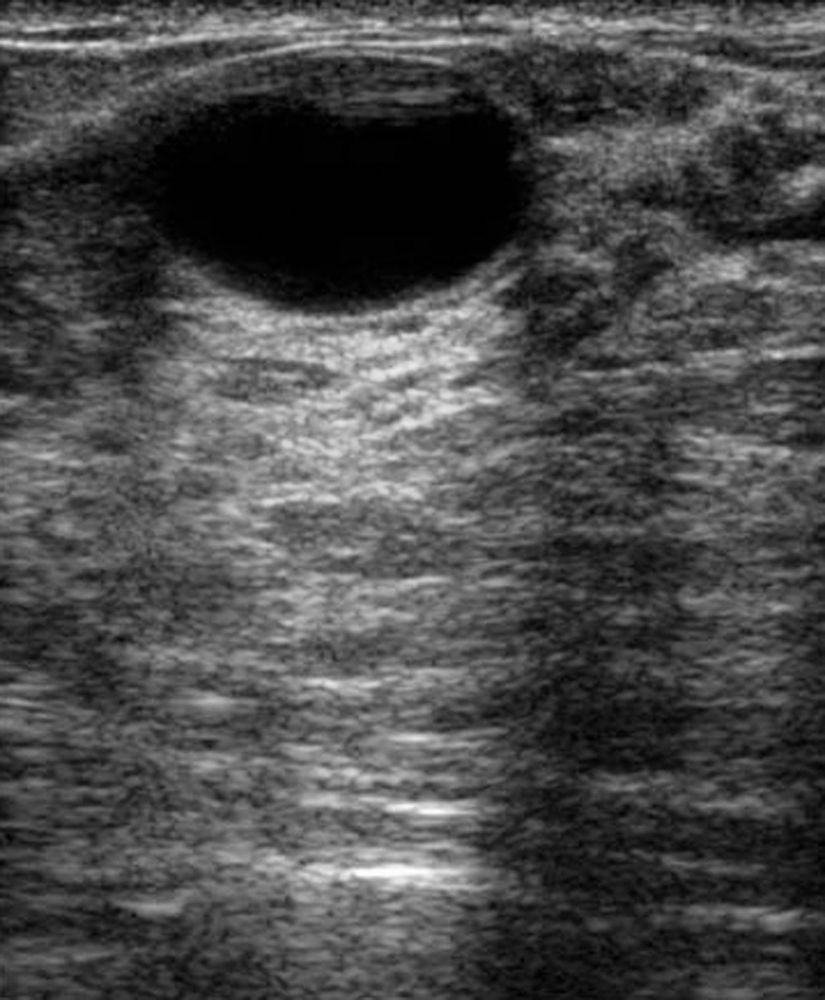

УЗИ диагностика кольцевидной поджелудочной железы: что важно знать